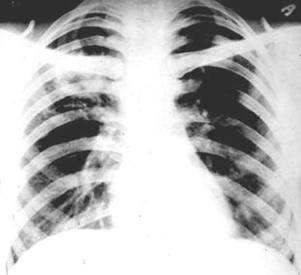

Рентгенодиагностика бронхопневмонии: Советы и примеры

Раздел: Альбом открытий